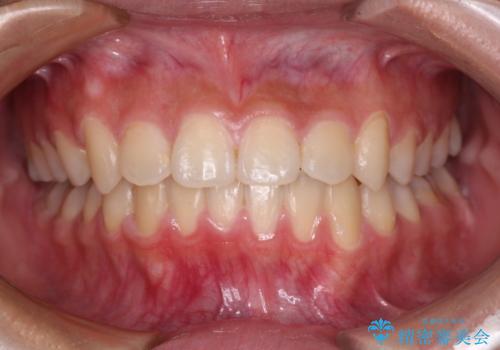

急速拡大装置で狭い歯列を骨格ごと改善 ワイヤー装置による矯正治療

- 1年6ヶ月

急速拡大装置を用いて上顎骨を側方に拡大し、上顎の叢生を解消するとともに下顎歯列拡大により下顎の叢生も解消することとしました。

急速拡大装置使用直後は著しいスペースが正中に発現するため、ワイヤー矯正を行いますが、今回は治療期間を短くしたいとのことで、上下全体をワイヤー装置にて矯正治療することとしました。